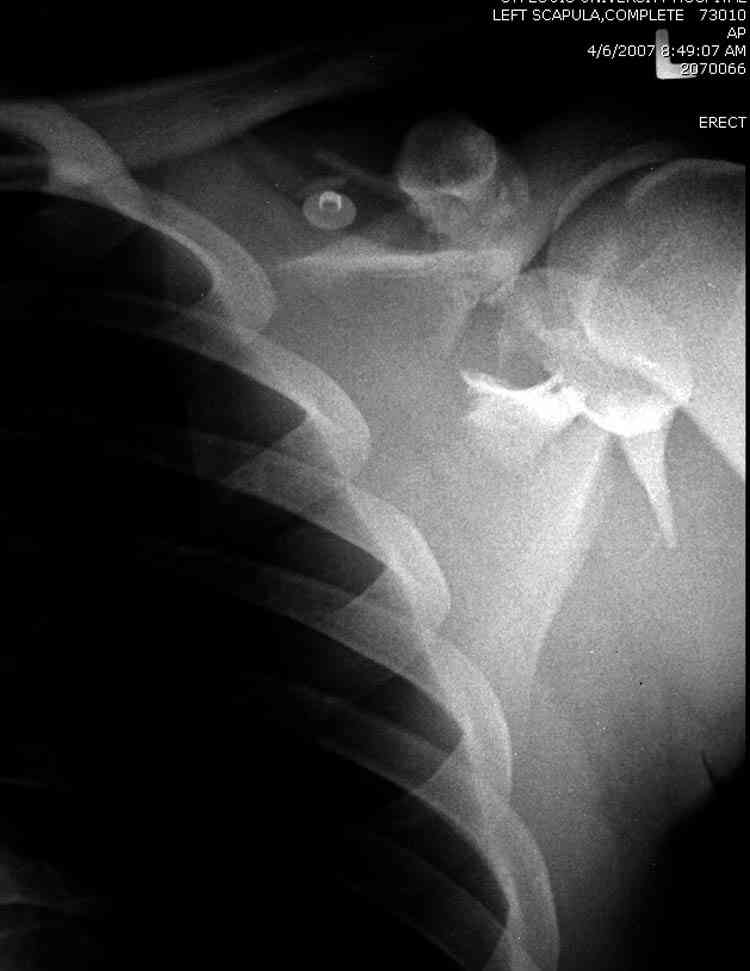

Если у вас имеется доказательство, что перелом лопатки изолированный, тогда нет необходимости операции, потому что стабильные изолированные переломы лопатки срастаются хорошо из-за хорошего кровоснабжения.

Для решения насчет оперативного вмещательства на лопатке сперва надо определиться с обьязательными ренгенологическими исследованиями, не менее трех стандартных проекций: прямая, аксиллярная и в позиции виде “Y”.

К-томографические и Трехмерные(3D)снимки крайне важны для определения внутрисуставных переломов и классификации.

Кроме анатомической классификации, переломы лопатки делятся на стабильные и нестабильные, внутри- и внесуставные и с вовлечением суставной поверхности.

Нестабильные внесуставные переломы лопатки типично сочетаются с переломами ключицы и ребер.

Также показания к оперативному вмещательству на лопатке появляются, когда смещения суставной поверхности медиально 9 и более мм и при угловом смещении суставной поверхности 40 и более градусов.